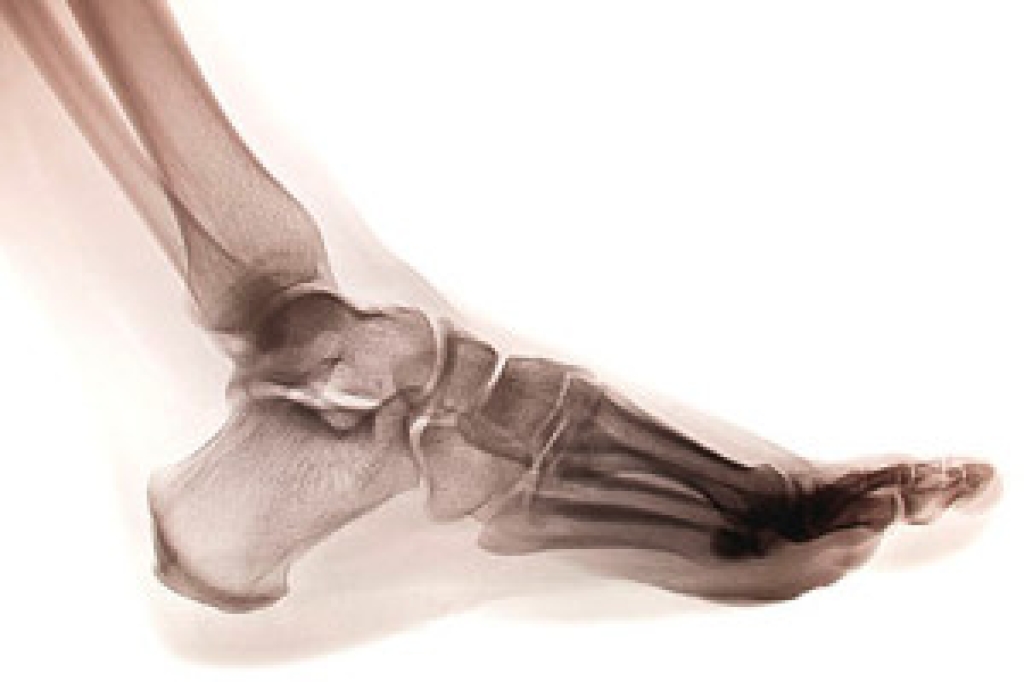

Some symptoms your child might be experiencing if they have a broken toe are swelling, redness, severe pain, and discomfort. These symptoms typically occur at the time of the injury. In more severe fractures, the bone may protrude from the skin, which is referred to as a dislocated bone. Broken toes can happen for a variety of reasons including: stubbing the toe against a piece of furniture, stepping off of a curb unexpectedly, or jamming it while participating in sporting activities. If the pain is extreme, an X-ray should be performed to determine the extent of the fracture. If your child has broken his or her toe, it is advised that you speak to a podiatrist who can discuss proper treatment options with you.

Although most people try to avoid foot trauma such as banging, stubbing, or dropping heavy objects on their feet, the unfortunate fact is that it is a common occurrence. Given the fact that toes are positioned in front of the feet, they typically sustain the brunt of such trauma. When trauma occurs to a toe, the result can be a painful break (fracture).